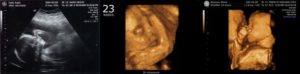

23 неделя беременности: что происходит с малышом | Развитие плода

Находясь в ожидании ребенка, женщина интересуется, что происходит с ее организмом, как развивается малыш, на что обратить внимание при вынашивании. 23 неделя беременности характеризуется изменениями и взаимодействием материнского организма и эмбриона.

Определение размеров малыша называется фетометрией. На 23-24 неделе рост плода достигает 29 сантиметров, а вес 450 грамм. Если раньше он напоминал запятую – большая голова и маленькие ножки, то сейчас его внешний вид все больше приближается к таковому у новорожденного.

В ближайшие 5 недель плоду предстоит большой скачок роста. Размеры плода на 23 неделе беременности можно сравнить с размерами папайи. Его длина от макушки до кончиков пальцев составляет около 29 см, а его вес приближается к отметке в 500 гр. Дети, рожденные на этом сроке, имеют 50% шанс на выживание.